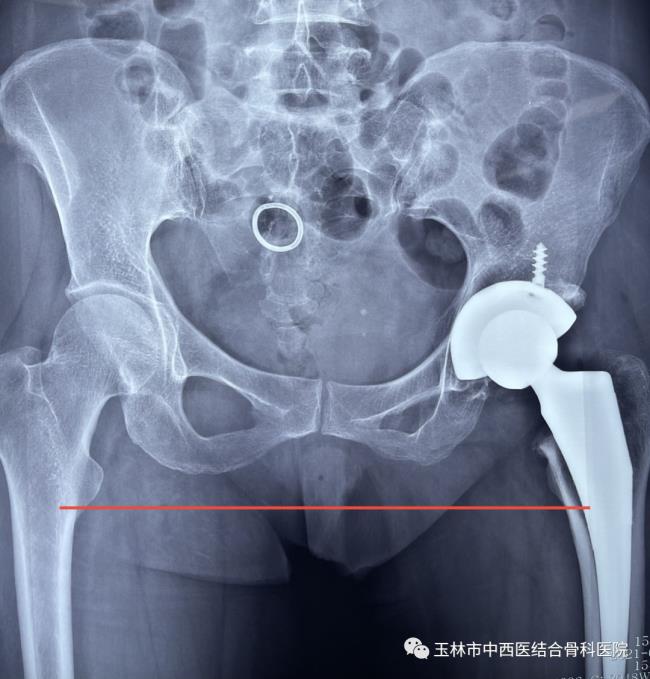

图一为患者术前DR结果

图二为患者髋关节置换术后DR结果

36岁的卢先生来到玉林市中西医结合骨科医院,入住髋关节一科,经该科黎观保主任和刘桐源医生询问病史、查体、阅片后诊断为“双侧股骨头坏死”,为卢先生制定了“直接前方入路(DAA)人工全髋关节置换术”的治疗方案。

手术当日,髋关节一科黎观保主任带领团队在麻醉科、手术室的配合下为卢先生进行了直接前路(DAA)微创人工右髋关节置换手术。由于手术创伤小,术中几乎没有出血,对肌肉组织损伤也非常轻微,麻醉苏醒后的卢先生便可立即自主活动髋关节,能够轻松抬腿了,而且自觉没有明显疼痛感。

术后第一天就可在病房内不扶拐行走,没有明显跛行步态以及任何姿势的限制,还能完成深蹲、盘腿等动作,连病房里的病友都感叹手术的成功。其实,这一切主要归功于DAA。